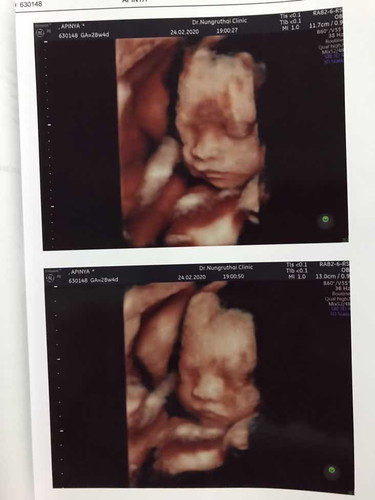

28+5 หมอบอกว่าน้องเอาสายรกมาคล้องคอ ? บ้านนี้ได้ลูกชายคร่า น้องแข็งแรงมาก น้ำหนัก 1200 กรัม ?